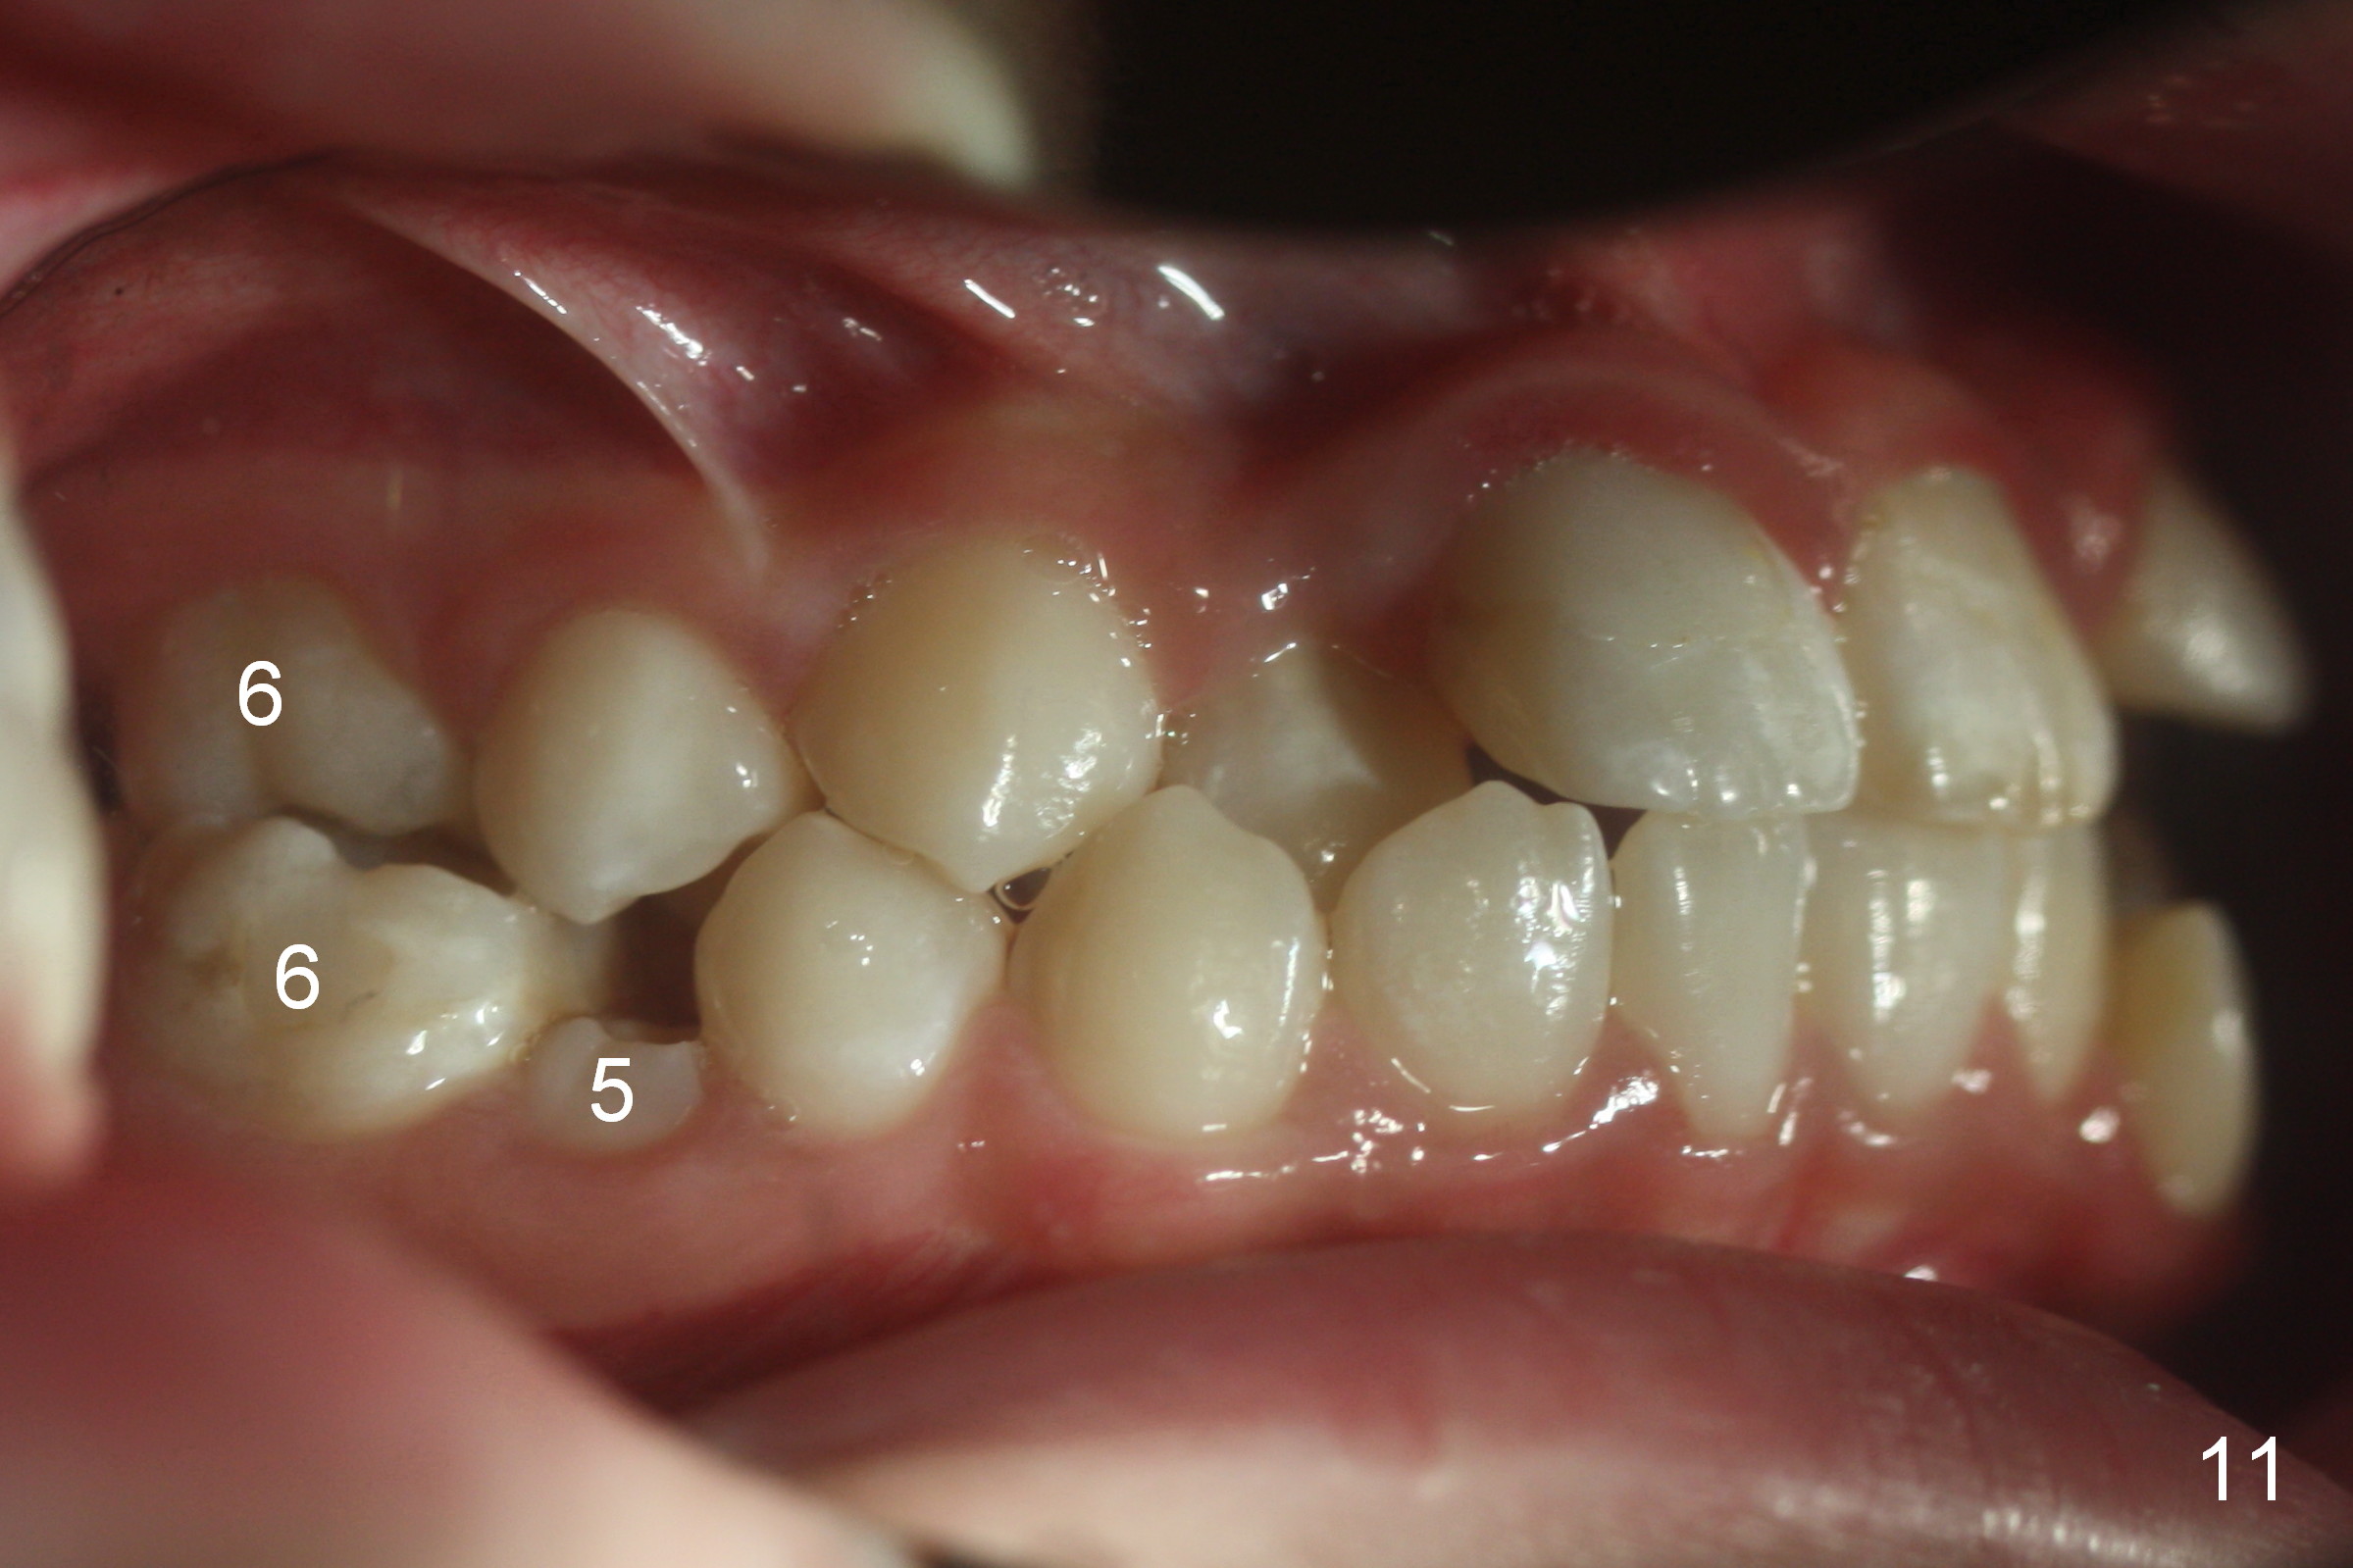

A 10-year-old girl with history of hyper-thyroidism has severe Class I malocclusion. She is ready for treatment. There is mild lip strain (suggesting anterior tooth protrusion, Fig.1,3). The facial and dental midlines coincide (Fig.2). Severe crowding is evident. Extraction orthodontics is indicated, either next to the most crowded areas (UR, LR4, Fig.6) or impacted ones (UL, LL5, Fig.10,11 (mirror view)).

Cross bite also exists at 6s (Fig.9,11). Place molar bands with sheets with the upper ones (potentially for palatal expander), with cleats with the lower ones (possibly for elastics).

The right canines are blocked (Fig.6,9). Use an elastic between them as early as possible to facilitate eruption, which is not done immediately post banding and extraction of R4s (Fig.12 (.014' niti wires)).